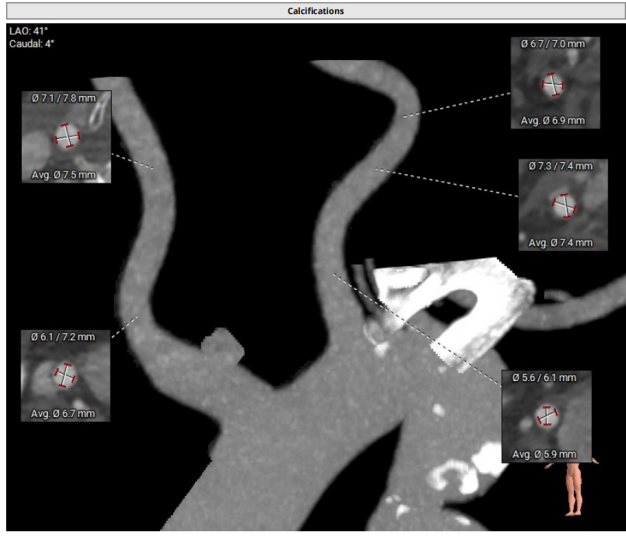

冠脉风险评估

双侧冠脉开口高度良好,瓣叶长度适中,综合瓦氏窦及窦管交界内径,冠脉风险较低。

外周入路分析

外周入路血管条件良好,内径可,无明显钙化;主动脉弓降主动脉出有明显狭窄和弯折,弓缩窄最窄处13mm,输送系统过弓可能有明显的困难,替代选择可以考虑颈动脉入路或者上长鞘拉直弯折。